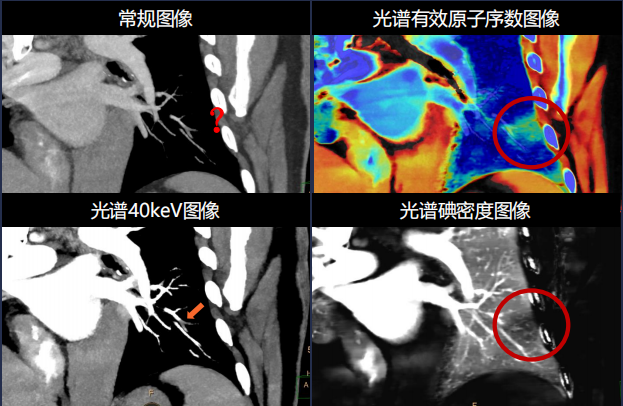

全新“逆向诊断” 精准诊断肺栓塞

皓克CT对于每一个检查的患者都可以提供常规以及光谱多参数数据,这 使得医生可以光谱有效原子序数图,碘密度图在直接判断肺功能(肺灌注) 是否存在异常;进而精准诊断肺栓塞,使得病患可以及时得到相应的治疗, 挽救生命,避免并发症。全新肺栓塞诊疗流程(改变肺栓塞诊断流程,从检出,到肺灌注,再到疗效评价,全程赋能)